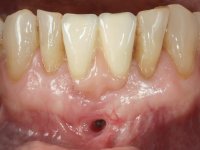

After an imaging study, the placement of two implants of 3.3 mm in diameter and 10 mm in length was planned. On the day of surgery, teeth 42 and 32 were extracted and the implant was removed. The implants were placed in the area of the alveoli, taking care to slightly lingualize their positioning. An impression was made using the open tray technique with the flap open for the fabrication of the immediate provisional bridge. While the impression was taken to the laboratory, tall healing screws were placed and the surgical wound was sutured. The patient waited 2 hours in the waiting room while the temporary bridge was made in the laboratory. An immediate screw-retained provisional bridge was placed and its seating was controlled by imaging. After 3 months, the final impression was made using an open tray technique. In this consultation, we took the opportunity to polish the temporary bridge with rubber cups so that the soft tissues could mature in better conditions. Information was collected to better characterize the monolithic structure in Zr. Color guides were used for the coronal and gingival ceramics. In the laboratory, a bridge was made in Zr. bolt-on that has been carefully characterized. After approval by the patient, it was definitively placed in the mouth. Tightening was performed with a dynamic wrench with a torque of 35 N. The holes were covered with Teflon and filled with composite resin.